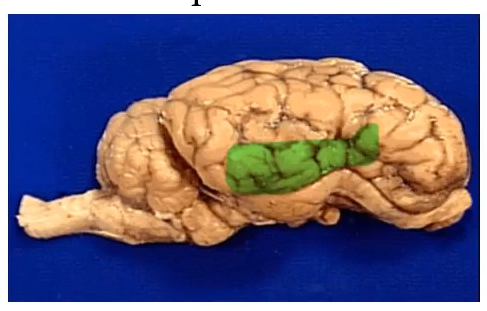

Name of Ridges Depression

Cerebral cortex

Coordinate language, thought, decision

“Grey matter”

Ridges: Gyrus

Depression: Sulcus

Lobe Name

Frontal Lobe

Lobe

Temporal Lobe

Lobe

Occipital Lobe

Lobe name

Parietal lobe

Name+ inside (not asking for lobe name)

Cerebellum

Has arbor vitae inside, sensory motor information